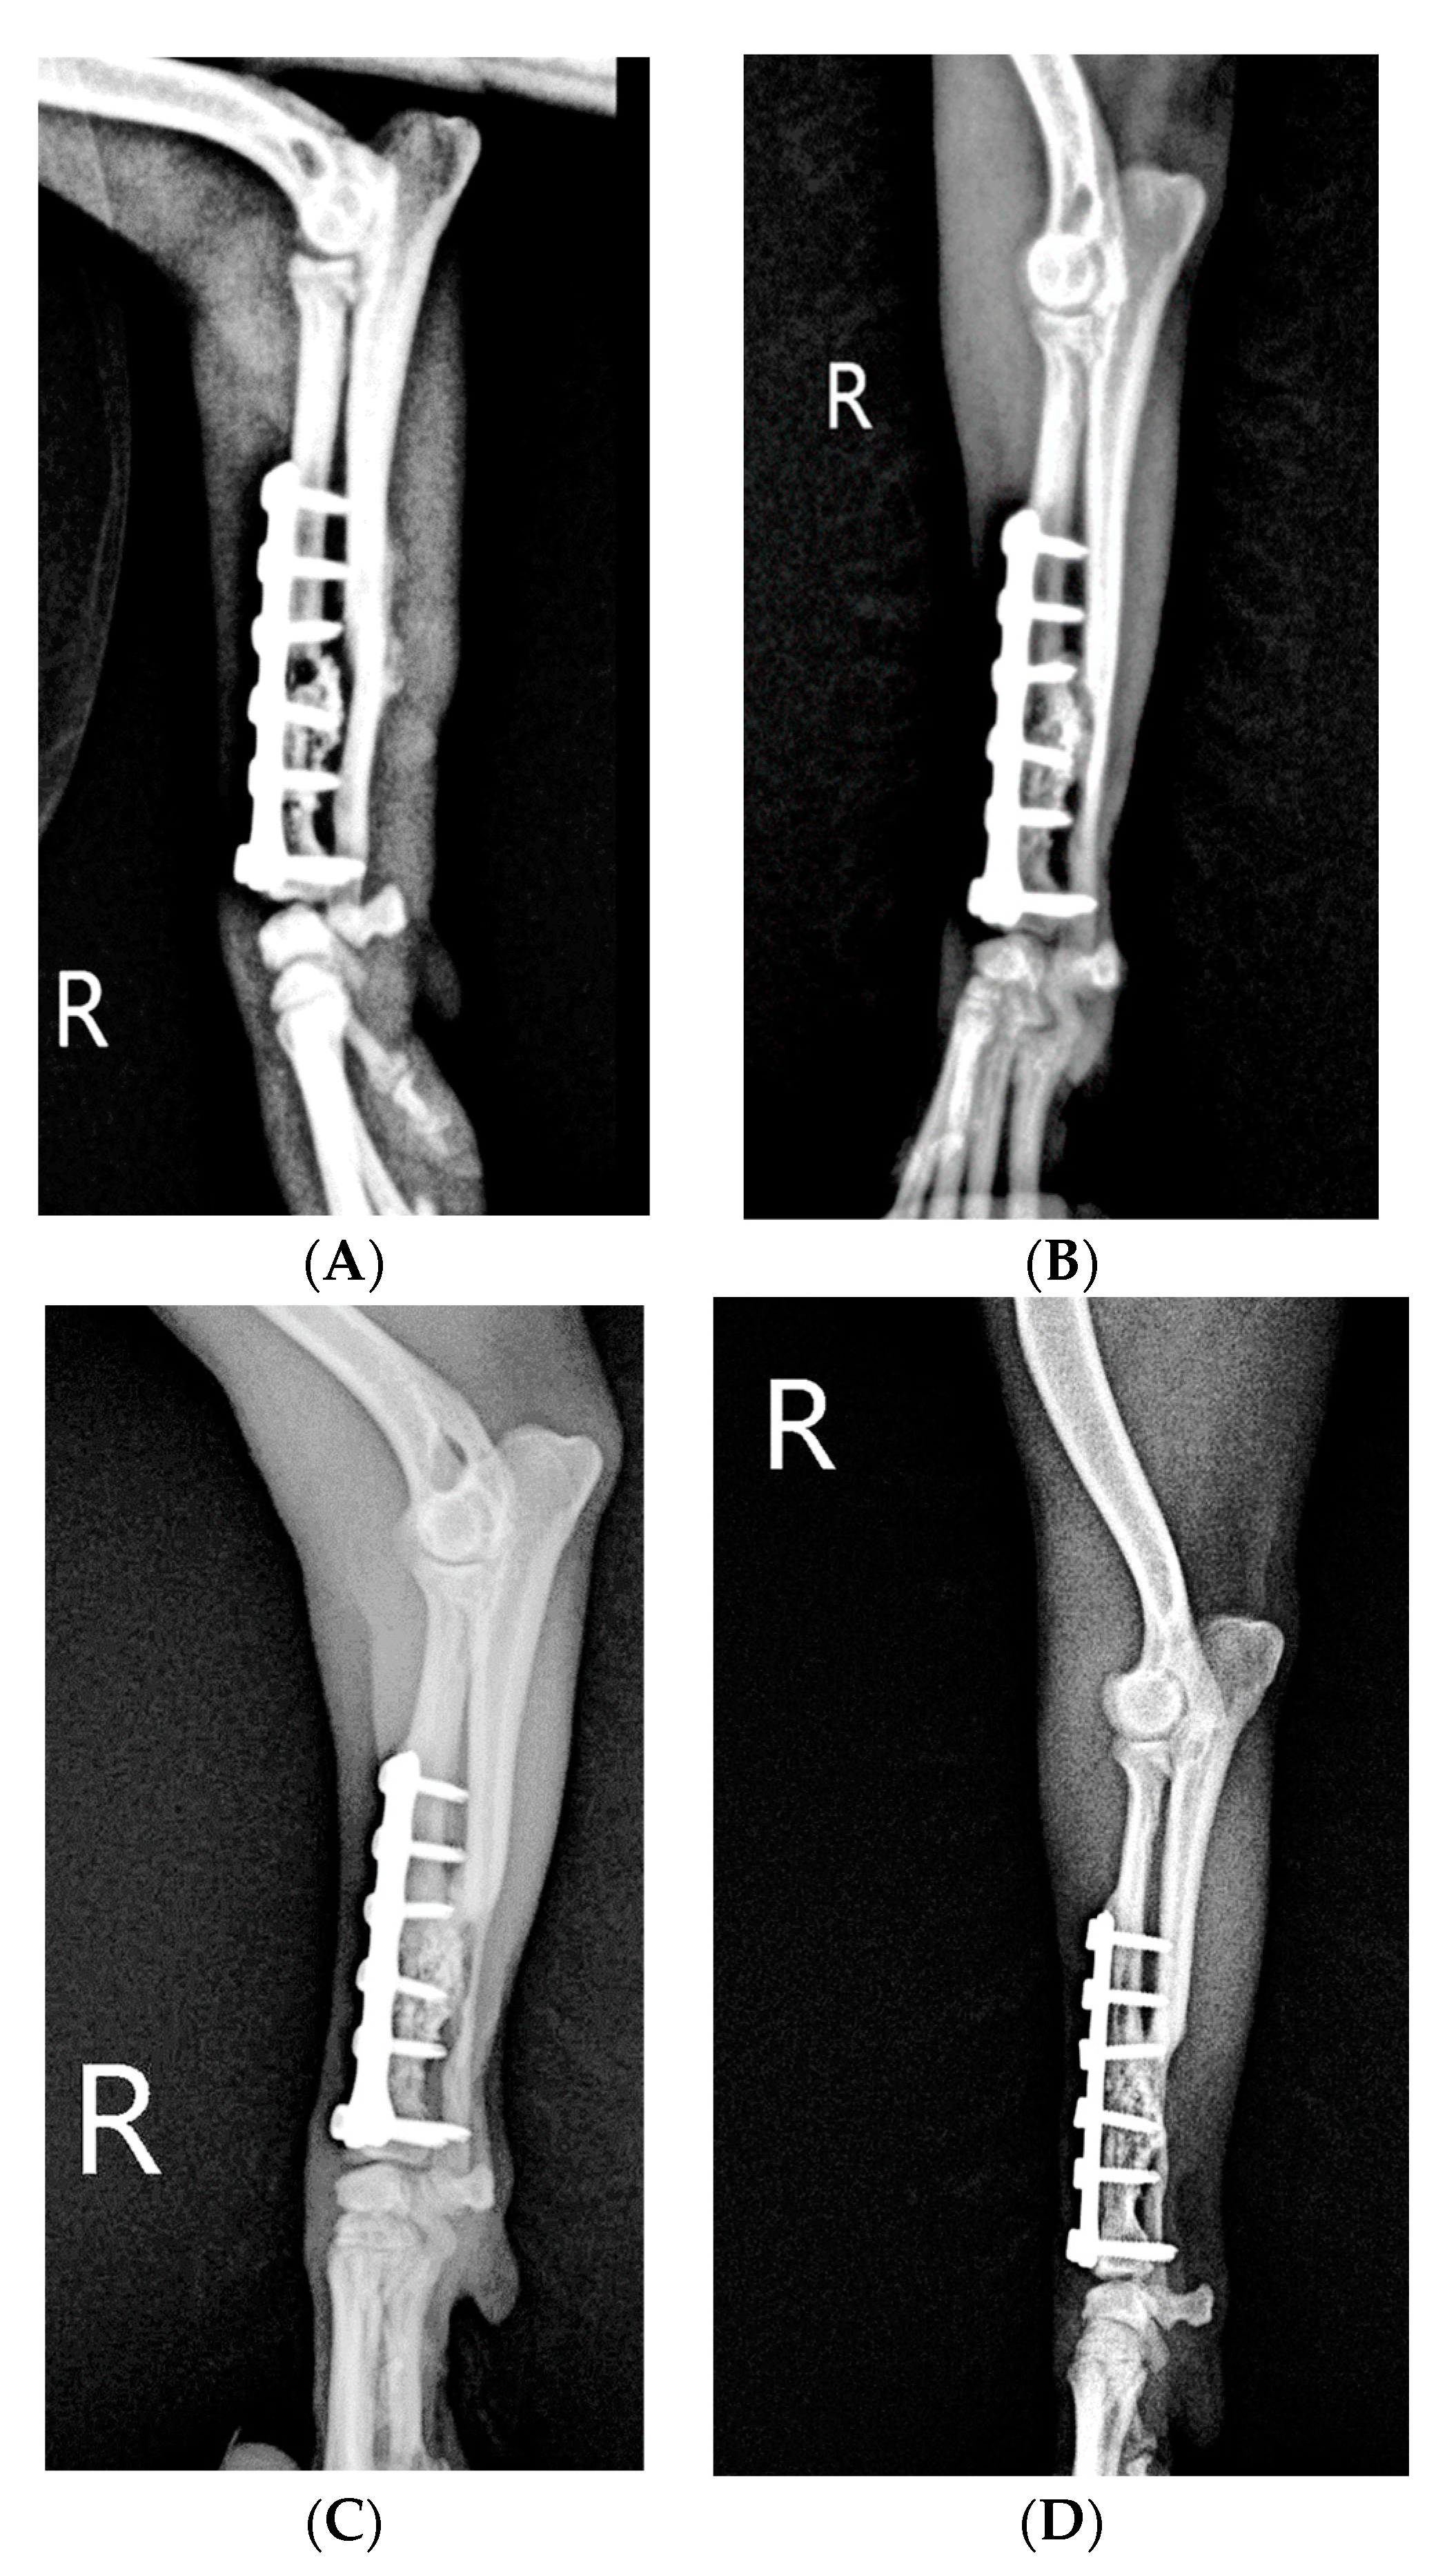

Slight weight bearing was allowed on postoperative day 65. On postoperative day 65, the callus was more abundant than before, the autologous ulnar bone fragment was fused with the existing radius, and the implant was stable. (Figure 5B). On postoperative day 142, the callus at the fracture end had invaded the ulnar bone fragments grafted in the fracture gap and was much thicker than before the initial presentation. Slight lameness was still observed upon walking and trotting (Figure 5C). On postoperative day 233, the transplanted ulnar bone was stable, with further increased radiopacity at both ends on the ventral side of the plate. There was no longer any lameness upon walking (Figure 5D).

Figure 5. Lateral radiographs of the right radius and ulna of a dog on days 1, 65, 142 and 233 (from left to right). (A) On day 1, there was an interfragmentary space in the grafted radius, with cancellous bone and BMP surrounding it. R: Right. (B) On day 65, the callus at the end of the fracture had fused with the autologous ulnar bone fragments, and the fracture ends were connected to the existing radius. R: Right. (C) On day 142, the callus from the fracture ends had invaded the ulnar bone fragments grafted in the fracture gap. (D) On day 233, the radiographs revealed the fracture ends of the radius in proper alignment and the bone plate in position. It was confirmed that the formed callus was connected to the cortical bone, which increased the bone density. R: Right.